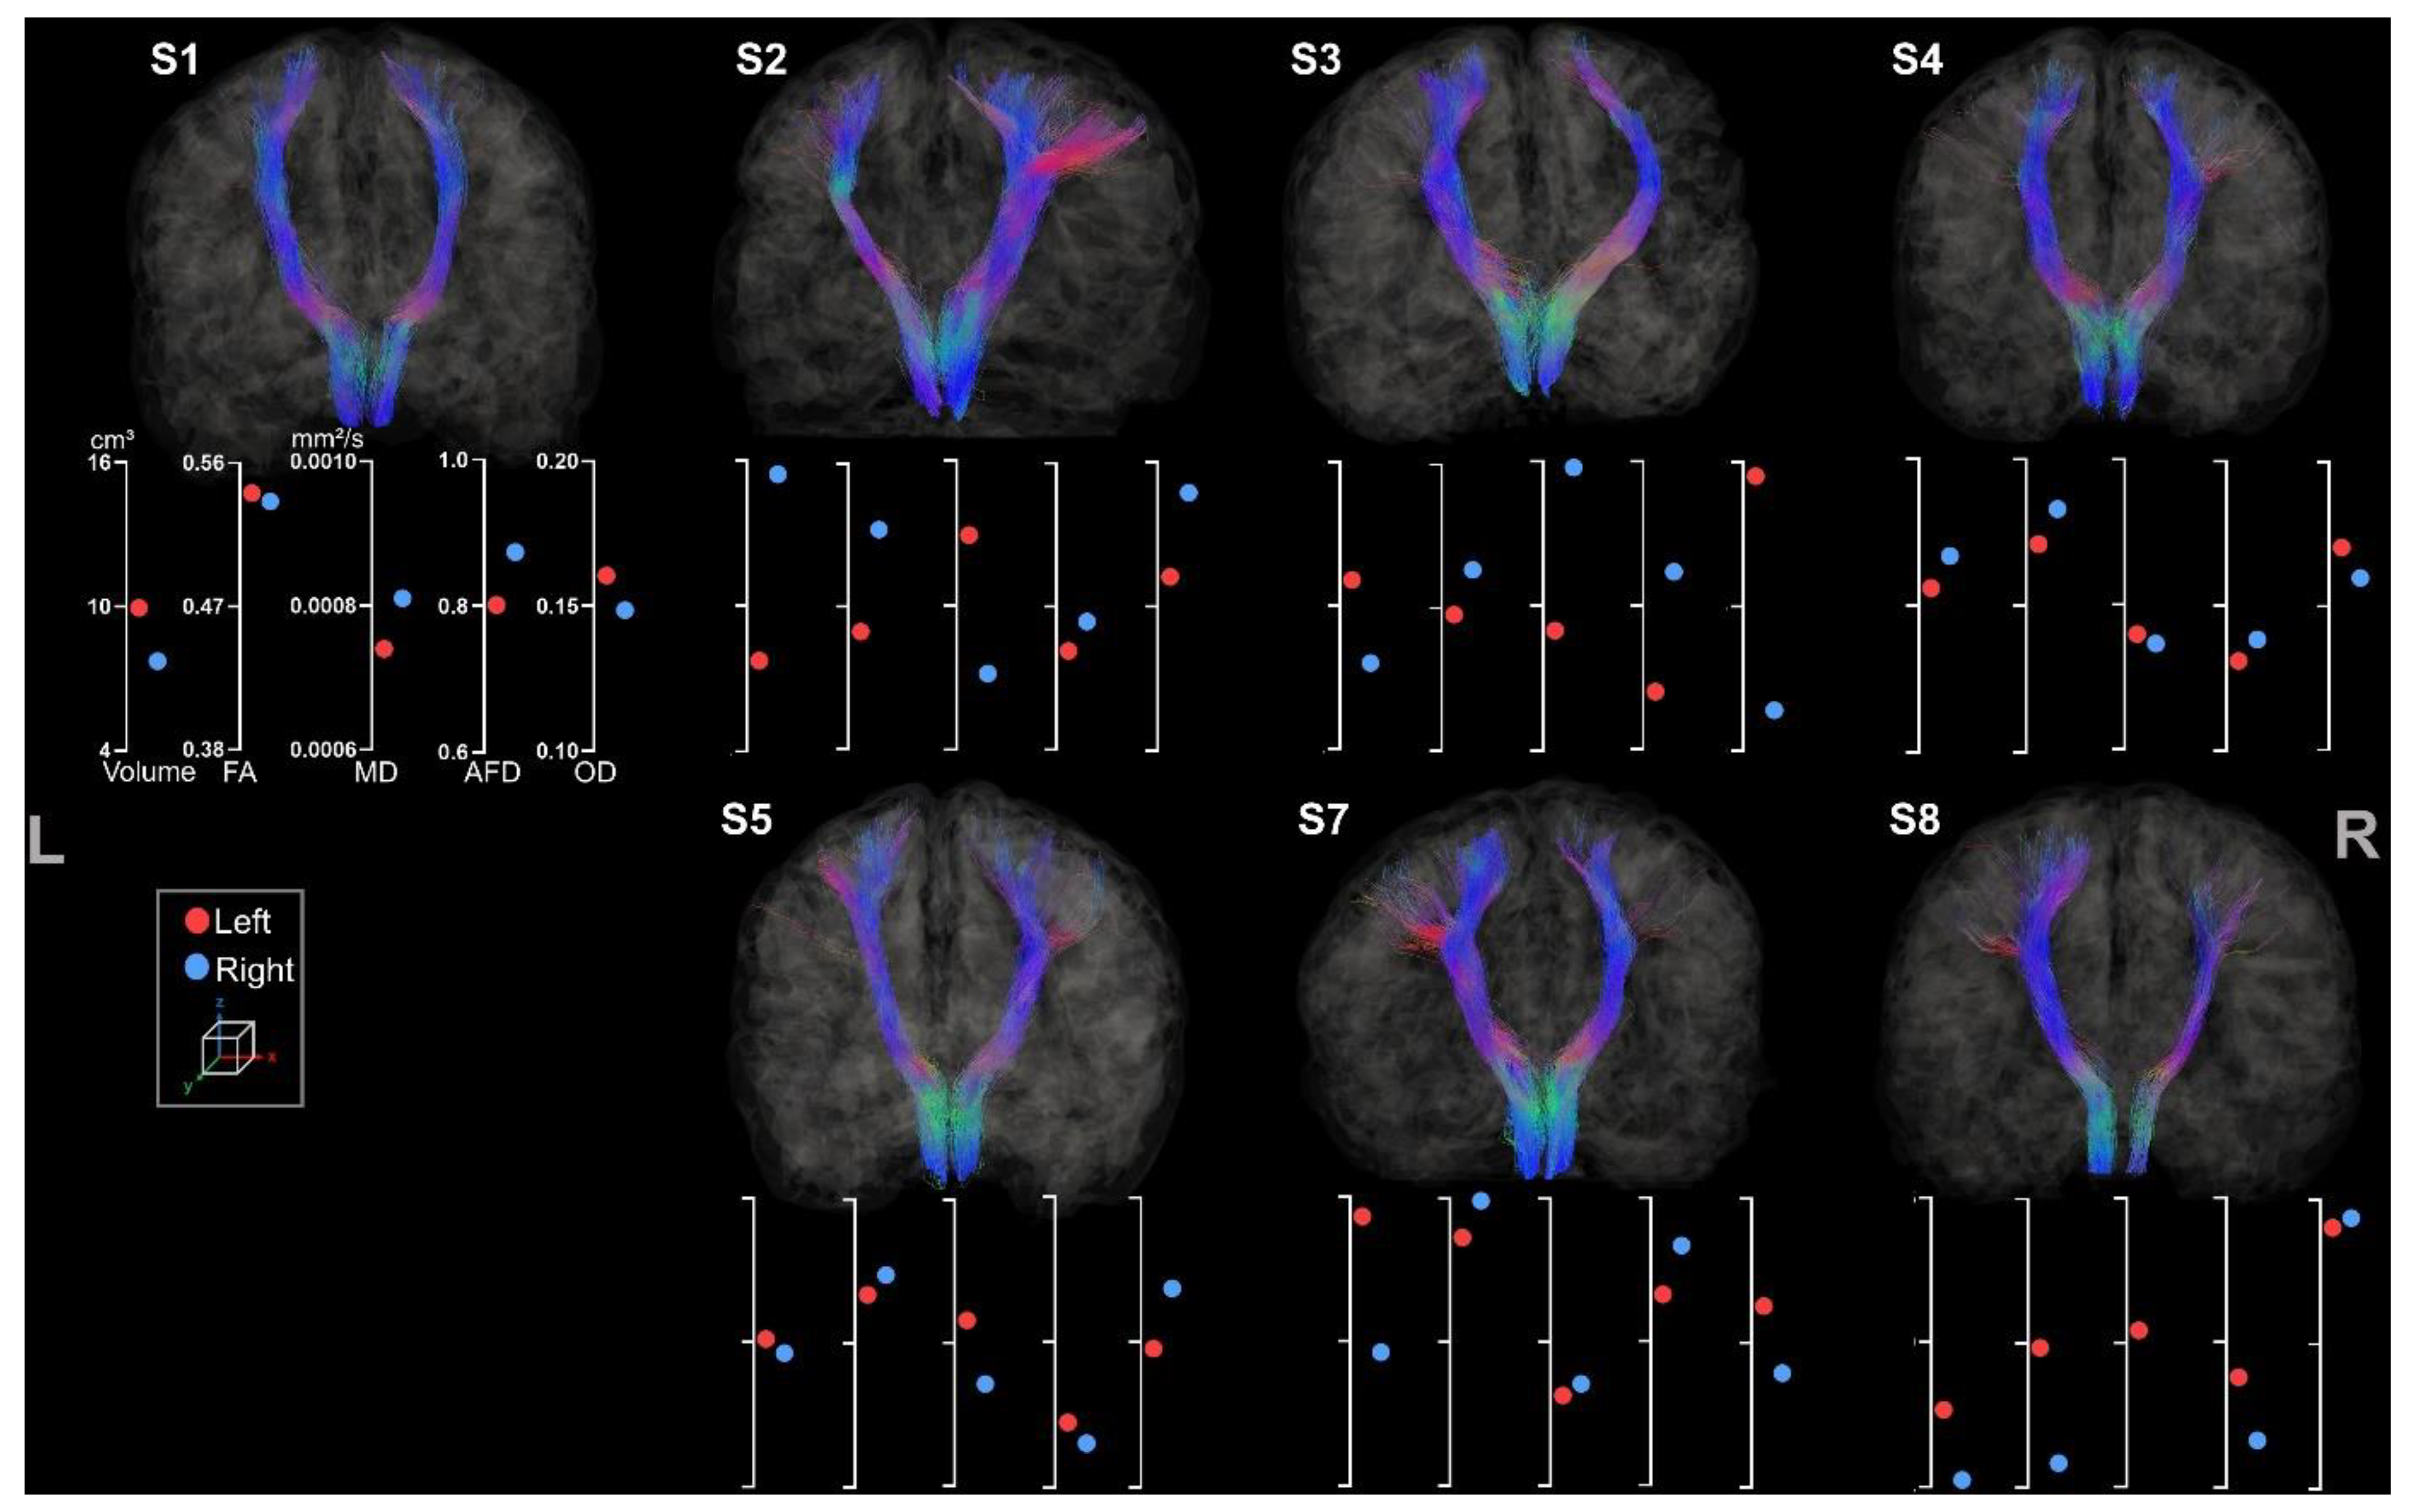

3.2.2. Corpus Callosum

3.3.1. Medio-Lemniscal Tracts Extraction